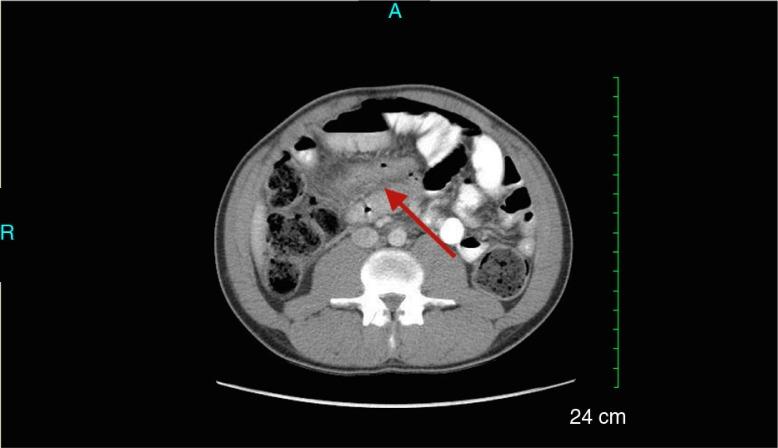

Behçet's disease (BD) is a chronic multisystem inflammatory disease most prevalent in Eastern Asia and along the Mediterranean basin, an area referred to as the 'Silk Road'. The diagnosis of BD is largely based on the International Study Group (ISG) criteria, which are more specific than sensitive. ISG criteria do not include intestinal manifestations, a feature more commonly seen in the West. Intestinal BD is one of several findings that are not typically seen along the 'Silk Road'. Herein we report a rare case of intestinal BD and compare Western versus traditional BD. A 25-year-old male with a history of painful oral aphthous ulcers, pericarditis, and diffuse papulopustular rash presented to the emergency department with two terminal ileal perforations. Pathology demonstrated mucosal necrosis with active inflammation and no chronic inflammatory changes. Post-surgical laboratory studies showed an elevated c-reactive protein of 35.57 mg/dL, erythrocyte sedimentation rate of 82 mm/h, and a positive anti-Saccharomyces cerevisiae antibody. Rheumatological workup including ANA, RF, PR3 antibody, MPO antibody, ANCA, SSA and SSB, Smith antibody, SCL-70, and anti-Jo-1 antibodies were all negative. His pericarditis symptoms improved with colchicine and prednisone prior to discharge. Our patient did not meet the current ISG criteria for traditional BD; however, he clearly showed findings typically seen in Western patients with BD, which include intestinal manifestations, cardiac involvement, and lack of pathergy reaction and ocular changes. Our investigation demonstrates that the clinical manifestations common to this disorder vary among geographic and ethnic populations. Commonly used criteria for the diagnosis of BD may not be sensitive for some populations, such as Western BD, potentially leading to underdiagnoses and mismanagement. Recognition and select inclusion of these differences may be one way to assist with diagnosing Western BD in the future. As our knowledge of BD continues to evolve, so must the population-specific criteria used to define BD.